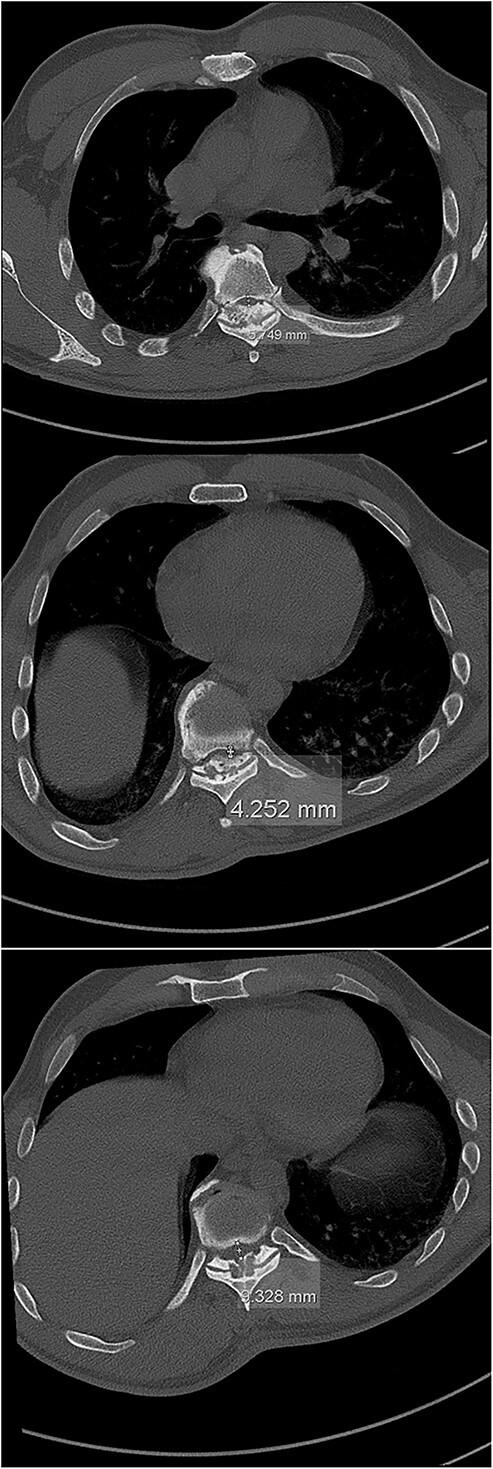

The ossification of the ligamentum flavum (OLF) presents a significant risk factor in the development of spinal cord compression in the (lower) thoracic spine, particularly in eastern Asian elderly males. The definite causes for OLF have not yet been fully uncovered, whereby age, genetics, metabolic disorders and mechanical stress are deemed among the most plausible pathophysiological factors in OLF. Spinal deformities (mostly kyphotic) are associated with an excess in tensile forces, which may lead to hypertrophy and OLF. This unique case of OLF-related acute paraplegia and progressive thoracic myelopathy in a Central-European male patient may indicate the role of a (kyphoscoliotic) spinal deformity in the initiation and progression of the OLF-related (thoracic) myelopathy. Promptly initiated surgical decompression and (partial) deformity correction may, along with proper subsequent intradisciplinary rehabilitation process, greatly improve the clinical outcome post-treatment, especially in terms of quality of life and residual pain.